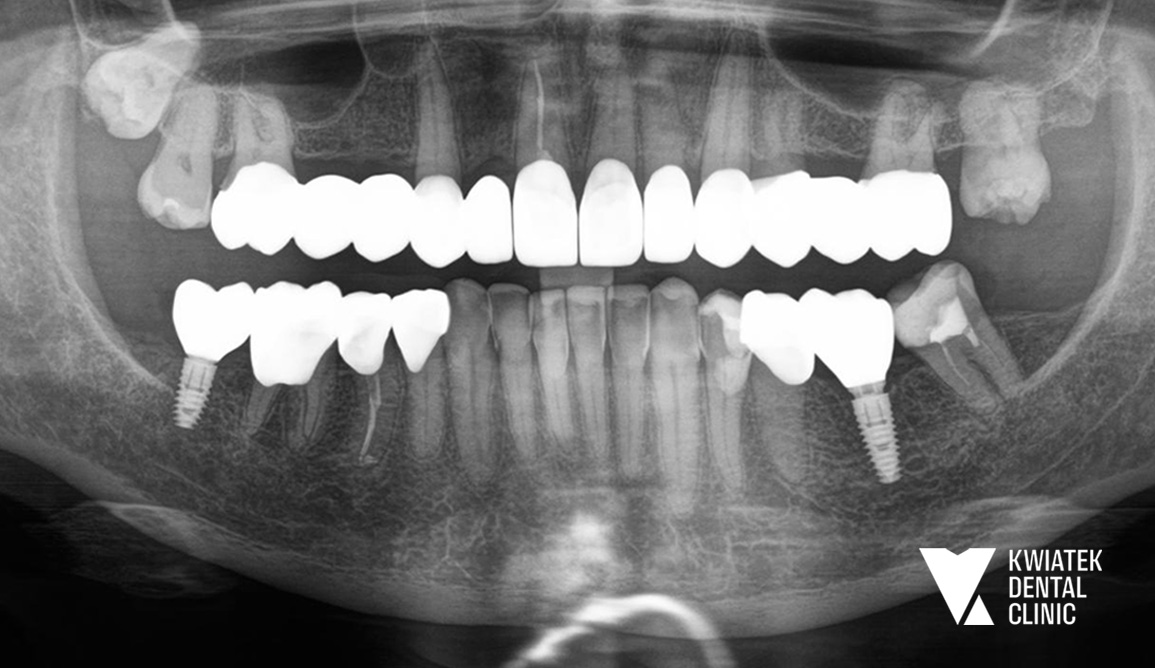

Wieloetapowa rekonstrukcja uśmiechu w leczeniu interdyscyplinarnym

PRZED

PO

Kolejnym ważnym etapem była odbudowa brakujących zębów w odcinku bocznym żuchwy. Wykonano zabieg implantacji w pozycjach zębów 36 i 47 z użyciem systemu implantologicznego MIS C1 oraz z zastosowaniem szablonu chirurgicznego i nawigacji implantologicznej. Po zakończeniu procesu osteointegracji wykonano odbudowy protetyczne na implantach oraz korony protetyczne na zębach własnych Pacjentki. Równolegle przeprowadzono estetyczną rekonstrukcję zębów dolnych metodą flow injection, która pozwoliła na odbudowę ich kształtu i przywrócenie prawidłowych proporcji uśmiechu. Całość leczenia uzupełniono zabiegiem wybielania zębów metodą gabinetową z zastosowaniem systemu Philips Zoom.

Efektem leczenia jest kompleksowa odbudowa zdrowia jamy ustnej oraz harmonijna poprawa estetyki uśmiechu Pacjentki. Usunięto ognisko infekcji, odbudowano brakujące zęby z wykorzystaniem implantów i przywrócono prawidłową funkcję zgryzu.